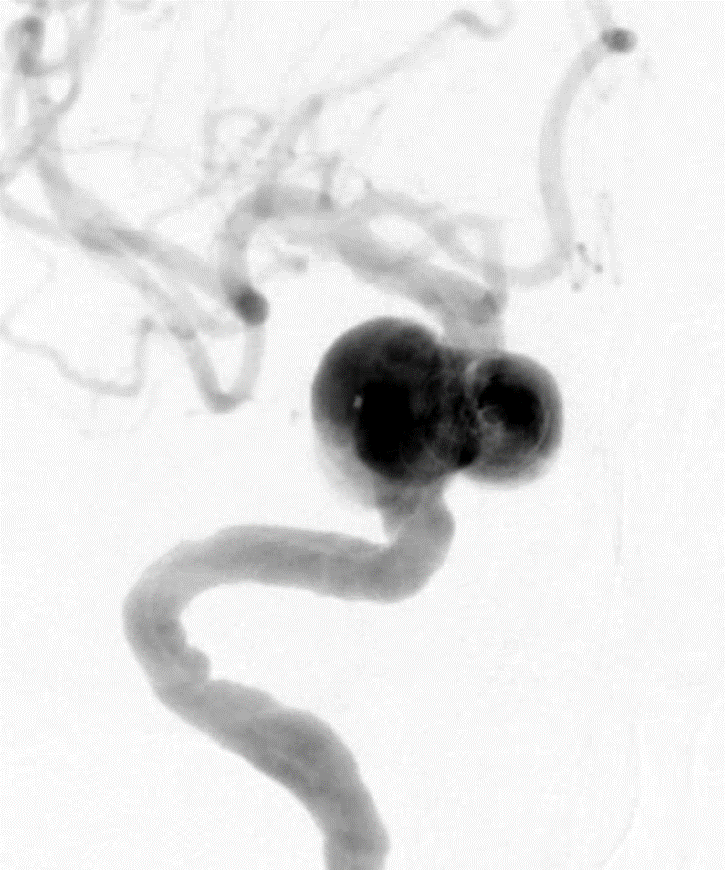

术前DSA造影:动脉瘤大小:4.9mm*4.8mm,动脉瘤颈:4.0mm;载瘤动脉远端直径:2.4mm,近端直径:4.0mm,长度:19.9mm。

DSA正位造影

DSA侧位造影

动脉瘤大小测量

载瘤动脉测量